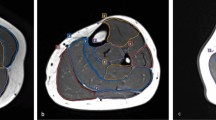

We used an ice-water phantom, a widely recognized standard for DWI, in all experiments [4]. The ADC of water at 0 °C was 1.1 × 10−3 mm2/s [15]. Our phantom consisted of five plastic rods with a 20-mm inner diameter inside a 3.4-L plastic container of ice water. The rods were filled with water and arranged in the plastic container with one at the center and four at the peripheral positions (Fig. 1) approximately 40 mm from the center.

Ice-water phantom used in this study. a Diagram of the phantom. Five water-filled rods of 20-mm diameter (dashed circles) are submerged in a plastic container filled with ice water. One rod is set at the magnet center, and the others are set at peripheral positions all approximately 40 mm away from the magnet center. b Diffusion-weighted image showing the centre of the phantom

The signal and temporal noise images consisted of the mean and standard deviation, respectively, of each pixel over five consecutive scans. Square regions of interest (ROIs) of 10 × 10 pixels were carefully set at the center of each water rod in both signal and temporal noise images (Fig. 2). Spatial mean values were calculated within the ROIs for both the signal and temporal noise images. According to the QIBA recommendation [14], the 95% confidence interval (CI) of the SNR was defined as follows:

ROIs for SNR and ADC assessment. ROIs on the signal image (a), noise image (b), and ADC map (c) of the phantom middle acquired using the 1.5-T scanner. The signal image and temporal noise image were obtained by calculating the average and standard deviation, respectively, of each pixel from five consecutive scans. The ADC map was calculated using b = 0 and b = 1000 images. The 10 × 10-pixel ROIs (white squares) are set at identical positions for each image